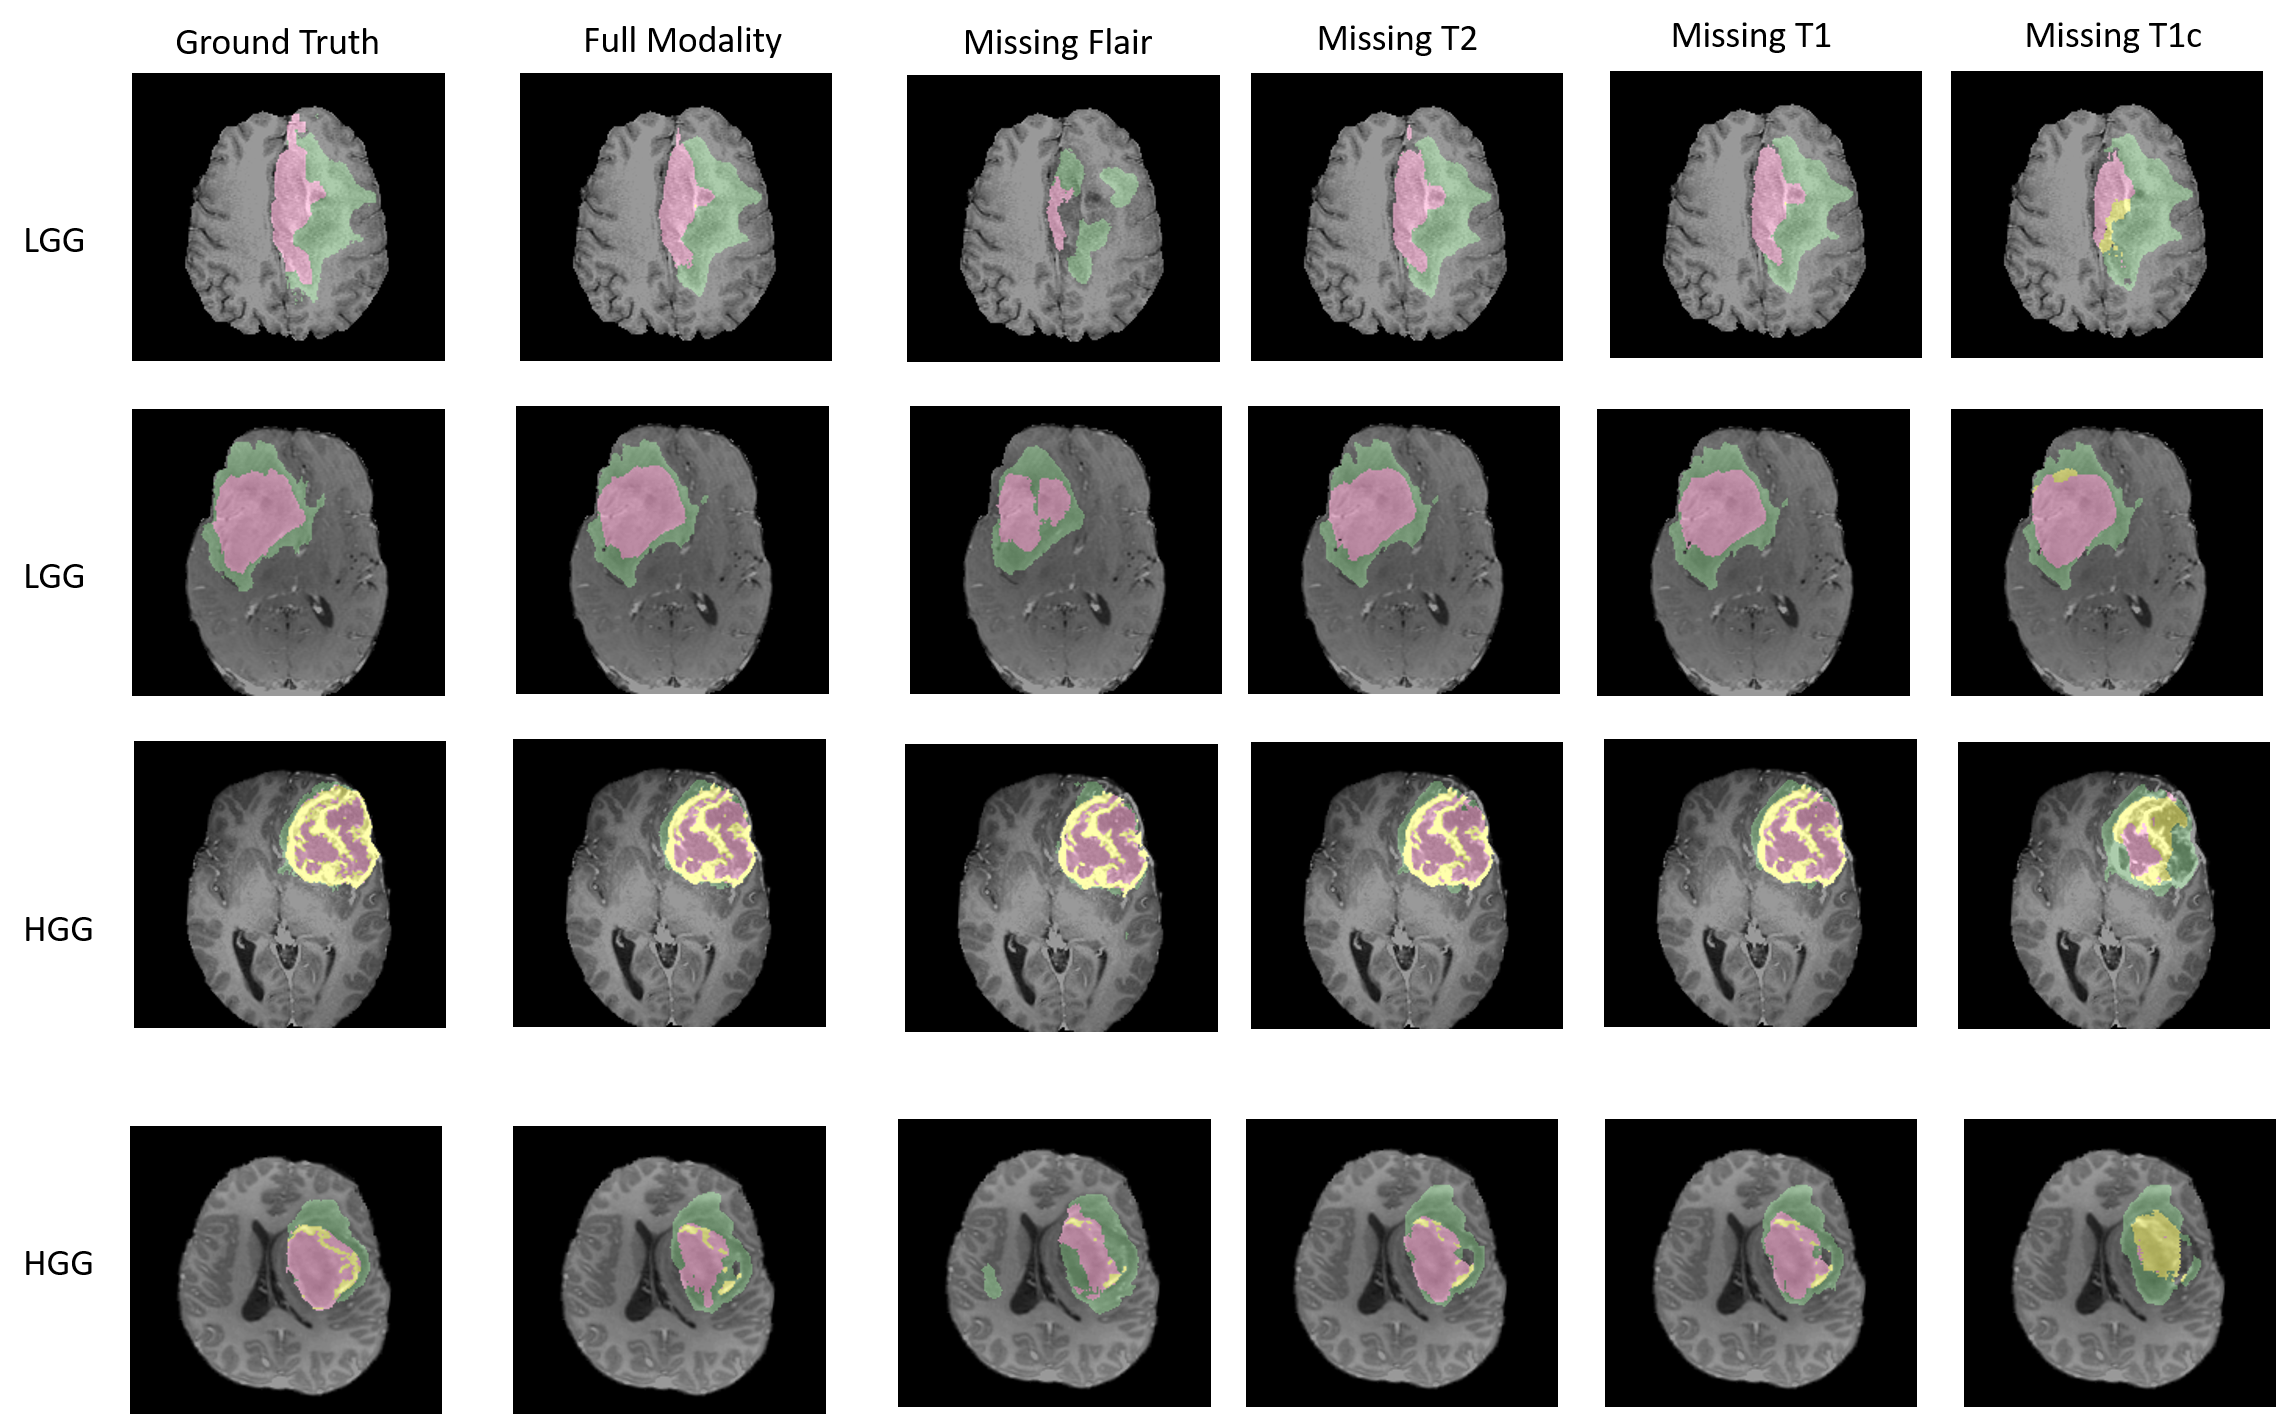

Secondly, we explored our segmentation results qualitatively by visualizing our results with ground truth segmentation. Our quality assessments include the segmentation region, boundary qualities and specificity/sensitivity. We evaluated our trained network’s segmentation qualities on both full channel inputs and missing channel inputs.

As shown in Fig. 3, missing Flair channel would result in a coarse locating on the whole tumor region. And missing T1c channel would result in mistaking tumor core and enhanced core region as non-core region.

To provide justification of domain adaptation loss term we introduce, we also provide an ablation experiment by training only on reconstruction loss in training process. Our baseline result is shown in Table 1. Distinct increases of Dice score in all categories are observed when trained with domain adaptation loss compared with the baseline. The qualitative visualization are consistent with the quantitative results as shown in Fig. 3.

Fig. 4 shows the contribution of each channel while predicting three types of tumors at pixel level. By weighting the prediction differences between inputting full channels and removing a specific channel, we visualize the influence of each channel to an individual segmentation label. Red color represents positive evidence, and blue color represents negative evidence from that channel to the segmentation label. We observed that, different channels contribute distinctly to different tumor types.